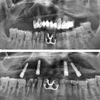

علاج الزرعات